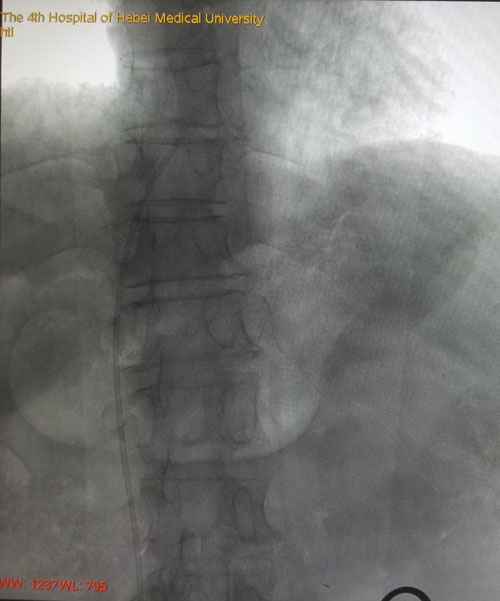

术后DSA评估导管尖端位置